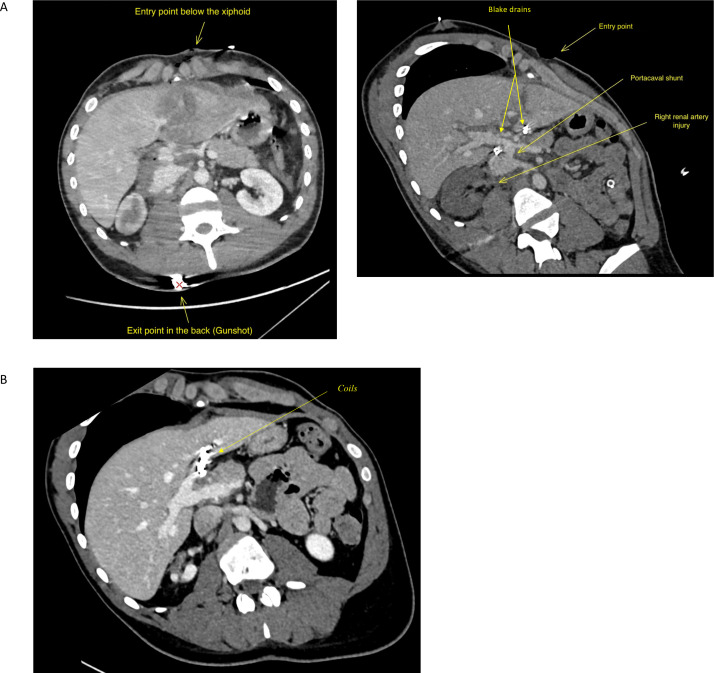

Traumatic portacaval shunt: a rare complication to be considered in patients with encephalopathy.